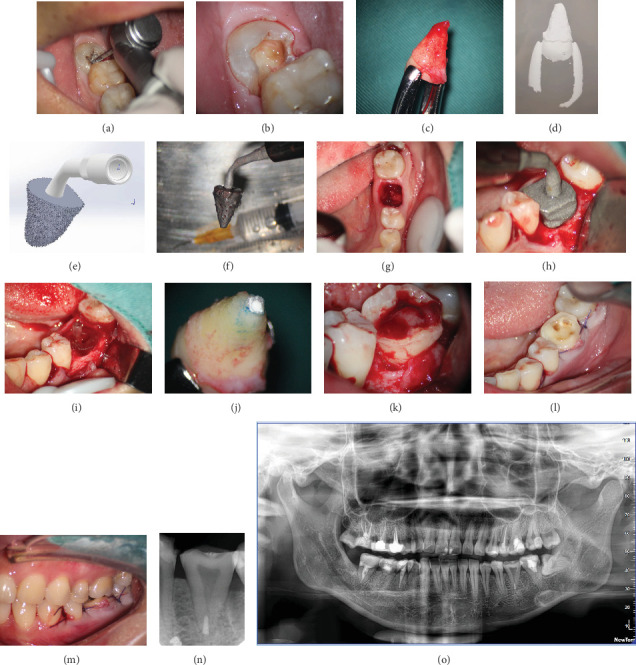

自体牙移植广泛应用于先天性缺牙或有不可逆损伤的牙的移植。本病例报告介绍了一种个性化的超声截骨术,它可以精确地准备,最大限度地减少骨创伤,增强移植牙的初始稳定性,并有助于良好的预后。手术过程如下:一名25岁的女性患者在19号牙齿上有一个瓷融合金属冠,由于严重腐烂而脱落,使牙齿无法修复。32号牙出现中等倾斜,导致31号牙腐烂。在提交治疗方案后,患者通过签署必要的文件表示知情同意,进行32号牙的自体移植以替代19号牙。第32颗牙齿被取出,并立即使用3Shape扫描仪扫描椅子。使用3D打印技术制作了一个定制的牙根形状的超声骨切开术,以匹配32号牙的形状。第19颗牙采用微创技术拔除。采用定制的3d打印超声骨切开术和计算机辅助快速成型树脂模型制备19号牙槽窝。然后将32号牙移植到牙槽内,并用8字形悬浮缝合线固定。为了防止在牙槽准备过程中因过热而损伤骨细胞和牙周组织,超声骨切开术设计了多孔水冷系统,有效地解决了这一问题。随访24个月后,移植牙符合成功标准,供体牙无病理性放光、牙根吸收或疼痛迹象。采用个性化超声截骨术制备的牙槽窝确保了与供牙的最佳贴合,保持了供牙的稳定性,并最大限度地减少了术后并发症。使用3D打印技术创建个性化的超声骨切开术代表了牙齿移植的创新进步,支持了该领域数字化和微创技术的发展。

Tooth autotransplantation is widely used to replace congenitally missing teeth or teeth with irreversible damage. This case report presents a personalized ultrasonic osteotome that enables precise preparation, minimizes bone trauma, enhances the initial stability of the transplanted tooth, and contributes to a favorable prognosis. The procedure is as follows: a 25-year-old female patient presented with a porcelain-fused-to-metal crown on Tooth #19, which had detached due to severe decay, rendering the tooth unsalvageable. Tooth #32 exhibited mesial inclination, resulting in decay of Tooth #31. After presenting treatment plan, the patient provided informed consent by signing the necessary documentation to proceed with the autotransplantation of Tooth #32 to replace Tooth #19. Tooth #32 was extracted and immediately scanned chairside using a 3Shape scanner. A custom-designed, tooth root-shaped ultrasonic osteotome was fabricated using 3D printing technology to match the shape of Tooth #32. Tooth #19 was extracted using a minimally invasive technique. The alveolar socket of Tooth #19 was prepared using the customized 3D-printed ultrasonic osteotome and a computer-aided rapid prototyping resin model. Tooth #32 was then transplanted into the socket and secured with figure-eight suspension sutures. To prevent damage to bone cells and periodontal tissues from overheating during socket preparation, the ultrasonic osteotome was designed with a porous, water-cooled system, effectively addressing this issue. After 24 months of follow-up, the transplanted tooth met success criteria, with no signs of pathological radiolucency, root resorption, or pain in the donor tooth. The alveolar socket, prepared with the personalized ultrasonic osteotome, ensured an optimal fit for the donor tooth, maintaining its stability and minimizing postoperative complications. The use of 3D printing technology to create a personalized ultrasonic osteotome represents an innovative advancement in tooth transplantation, supporting the development of digital and minimally invasive techniques in this field.